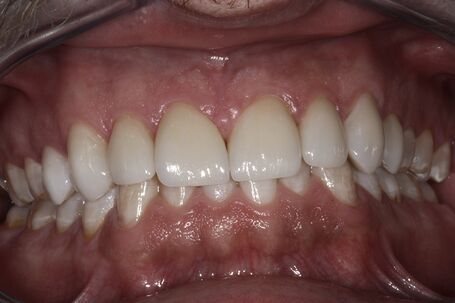

Veneers nach erfolgreicher Behandlung

nach der Behandlung